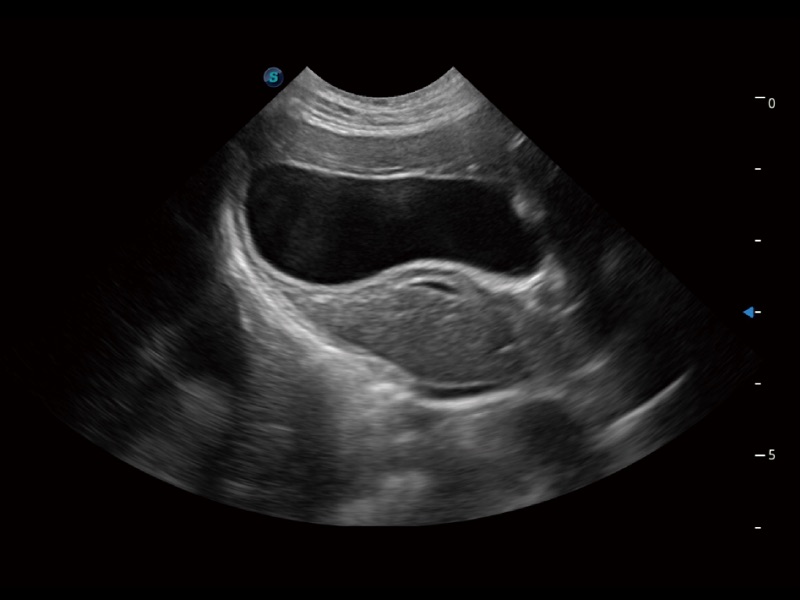

猫、中小型犬及小型异宠动物

ProPet 70 进一步提升了微米成像算法,更加注重对基础原始图像的还原和保留,在有效减少斑点噪声、增强组织边界显示的同时,避免过度优化丟失真实的解剖信息。

ProPet 70专为动物医生设计,对不同的动物体型和生理结构作出了针对性的优化。通过动物影像专用软件,可满足个性化的应用需求,帮助动物医生获得更精确的诊断数据。

为精细结构及组织边缘提供高清晰度的图像和更大的成像视野。帮助减轻医生的用眼疲劳,快速精准获得测量的数据。